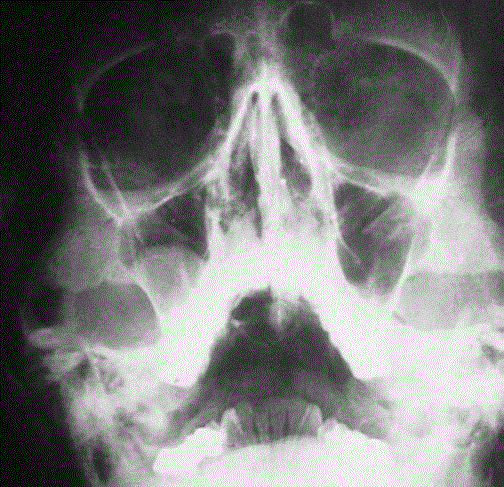

Beschreibe Röntgenbild

–> Auflösung der normalen Architektur des Unterkiefers links von der Kieferwinkelregion bis zum Processus coronoideus reichend. Bei größtenteils osteolytischem Charakter mit vereinzelten sklerotischen Arealen fällt eine Spikulaebildung vor allem crestal im Bereich des Kieferwinkels als typisches radiologisches Zeichen eines Osteosarkoms

Diagnose: Osteosarkom

Zu den radiologischen Zeichen Osteosarkom gehören die Größenzunahme des Knochens mit schlechter Abgrenzbarkeit, Kortikalisdestruktionen, Sklerosen, Osteolysen, Periostreaktionen, Spikulae und die Arrosion von Zahnwurzeln beziehungsweise die Verlagerung von Zähnen.